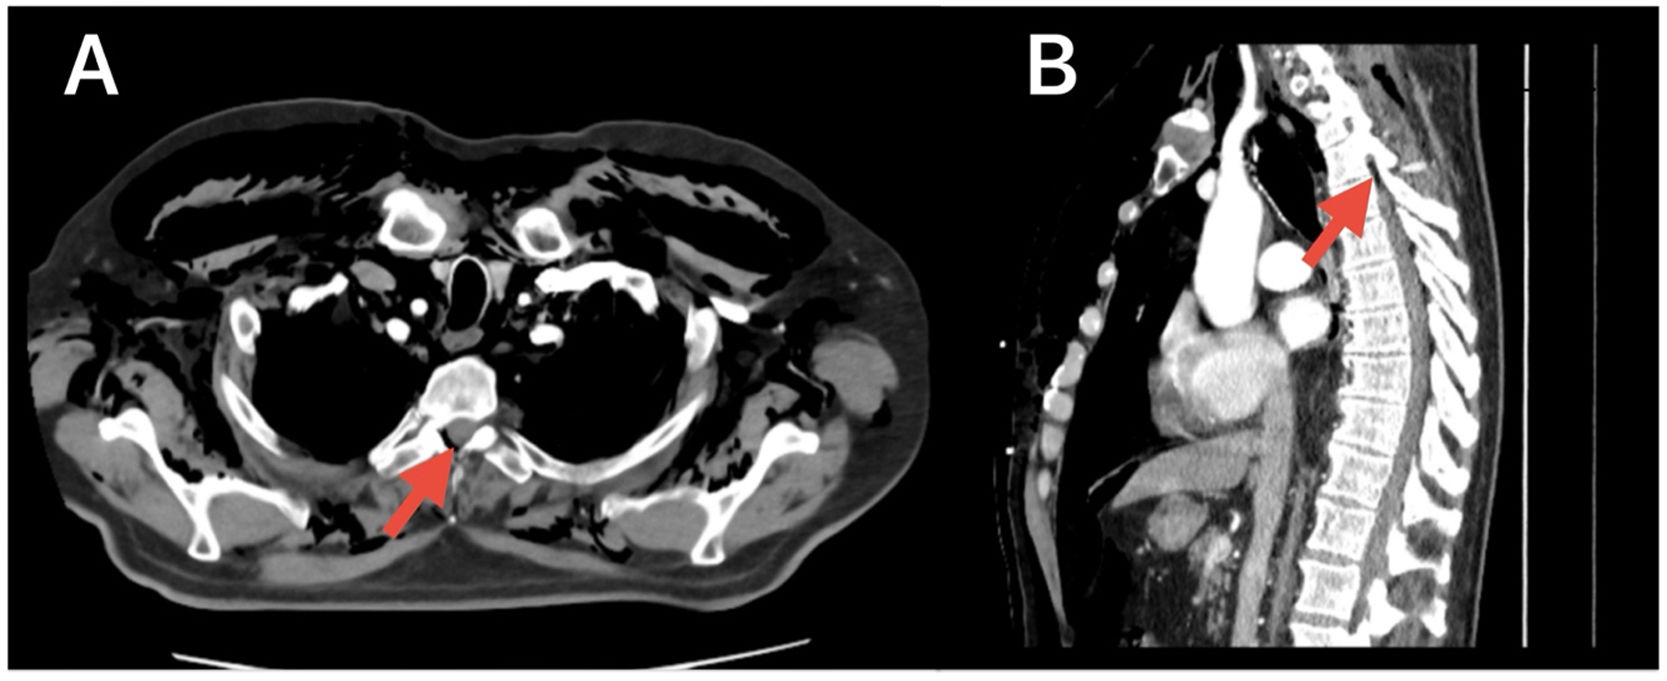

A 68-year-old man with no relevant medical history was admitted for atypical pneumonia and developed subcutaneous emphysema after a coughing episode. Computed tomography (CT) revealed extensive subcutaneous emphysema dissecting the cervical and thoracic fascial planes, air within the spinal canal (Fig. 1), small bilateral pneumothoraces, pneumomediastinum, and pneumopericardium. Pneumorrhachis is air in the spinal canal (epidural or subarachnoid space). Its etiology may be iatrogenic, traumatic, or spontaneous. It is usually asymptomatic and does not tend to migrate [1]. Diagnosis is based on imaging, preferably CT. Spontaneous pneumorrhachis is rare and usually does not require intervention [2].